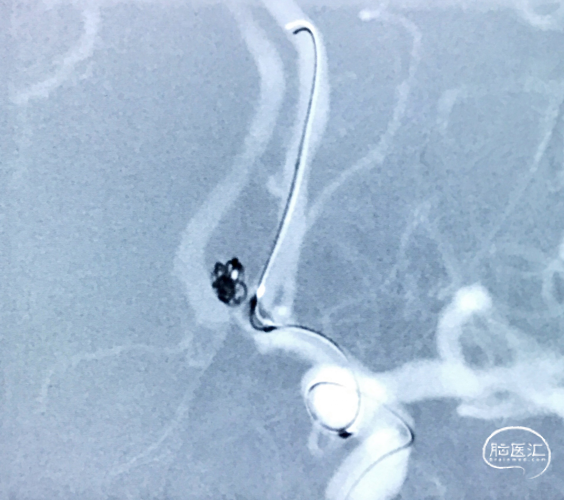

成篮后,将第一枚弹簧圈解脱,然后充盈球囊,让弹簧圈更好的进入瘤腔内,之后在球囊辅助下,分别填入Axium™ QC-3-4-3D、2-6、Axium™ QC-2-3-HELIX 弹簧圈各一枚进行填塞,最后填入两枚Axium™ QC-1.5-2-HELIX 弹簧圈进行收尾

球囊辅助下栓塞

在球囊辅助下,弹簧圈稳定地填塞进入动脉瘤,动脉瘤实现致密栓塞

术后造影

术后造影显示,动脉瘤完全栓塞,Rayond分级-1